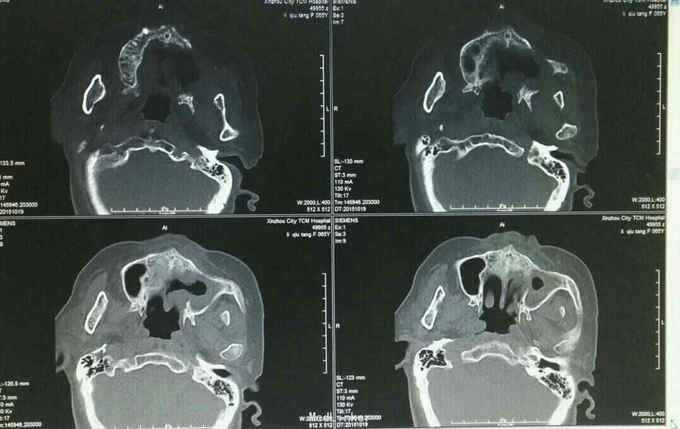

主诉:左上牙龈癌术后2月半余 病史:患者,女65岁,详见图:

查体、辅助检查见图:

诊断:左上牙龈癌术后复发 治疗:2015.10.21CT引导下行碘125粒子植入术,图为术前定位